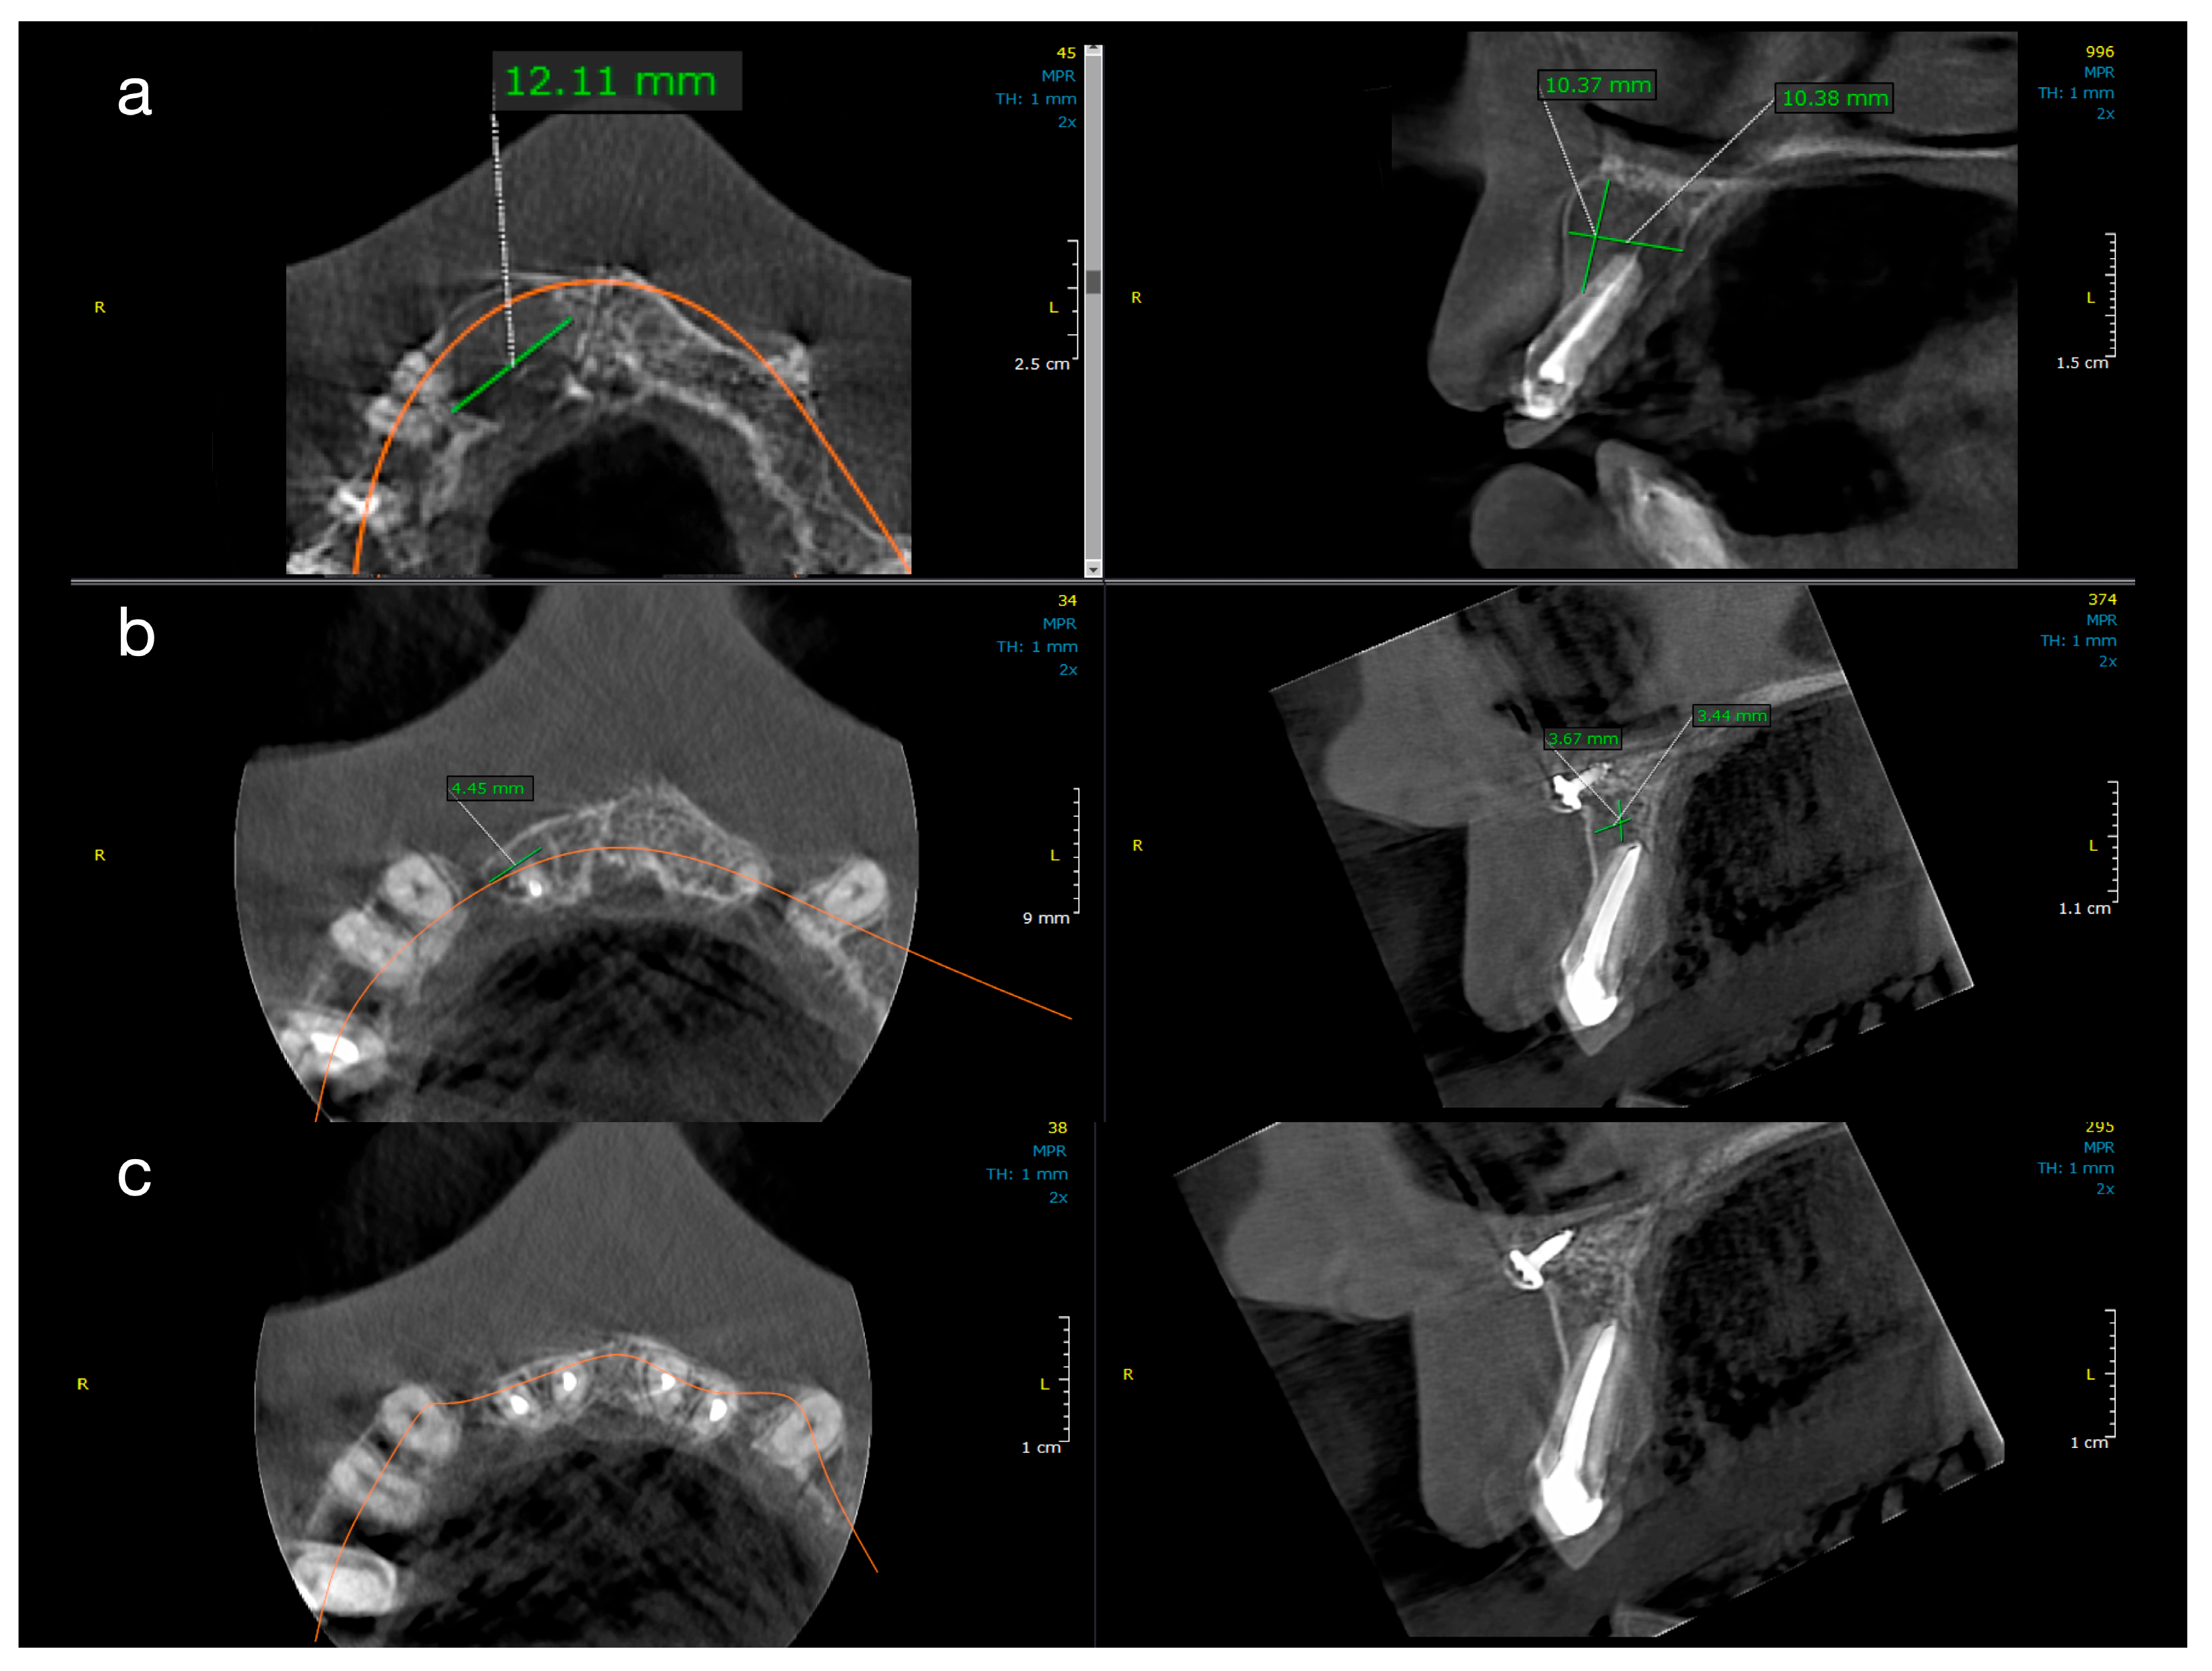

Nonsurgical Endodontics and Decompression-Based Management。CHX38 SQBD-3 Series | KOBE。SKX LEAGUE -。断捨離中の為、写真を撮ってアップしたら収納いたしますので、サイズの確認は各自検索してご確認ください。。THE TRADE MARKS JOURNAL December, 2012 - IPO Pakistan